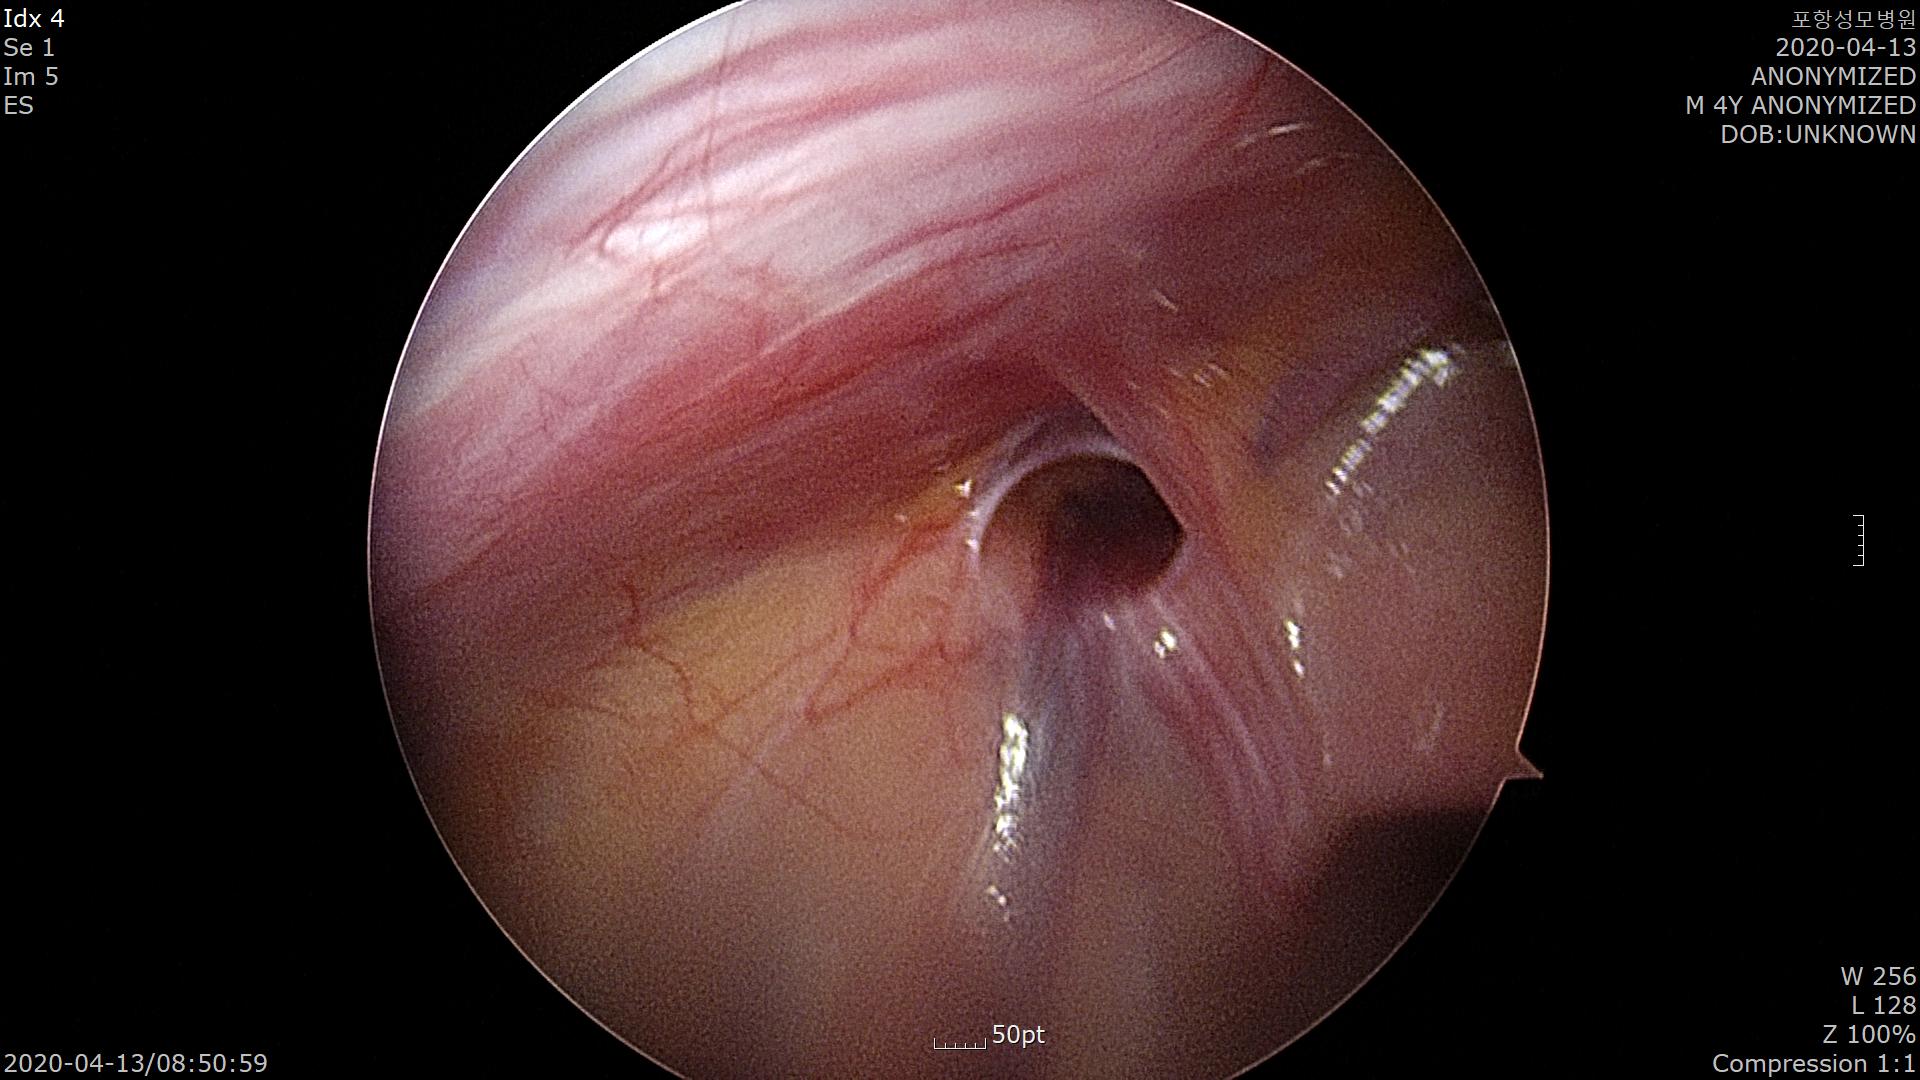

특수한 바늘을 이용하여 고위결찰(High ligation)을 시행합니다.

탈장구멍이 잘 막힌 모습입니다.